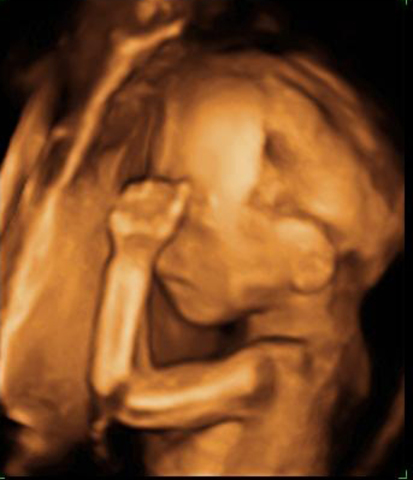

Desarrollo del feto en la semana 20: Ya están formados los órganos vitales

Se empieza a formar el paladar y las papilas gustativas se encuentran en toda la boca y no solo en la lengua, sino alrededor de ella, en el área de los labios e incluso en las mejillas.

El bebé ahora chupa el pulgar, juega con el cordón umbilical y se entrena con sus puños como un boxeador. Estos movimientos tienen un objetivo: ejercitar la musculatura en desarrollo e ir entrenándose